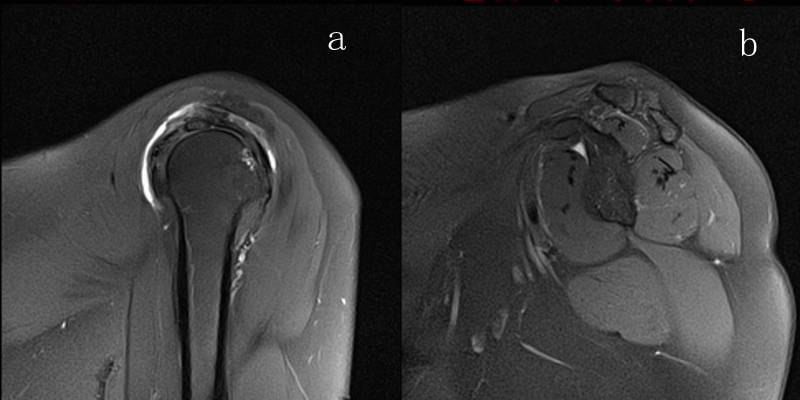

2、MRI检查

MRI目前是诊断肩袖疾病中最常用的检查,可以直观的观察肩袖肌腱。

图23 横断位a.正常肩胛下肌;b.肩胛下肌损伤

图24 a.肩袖全层撕裂;b.正常MRI